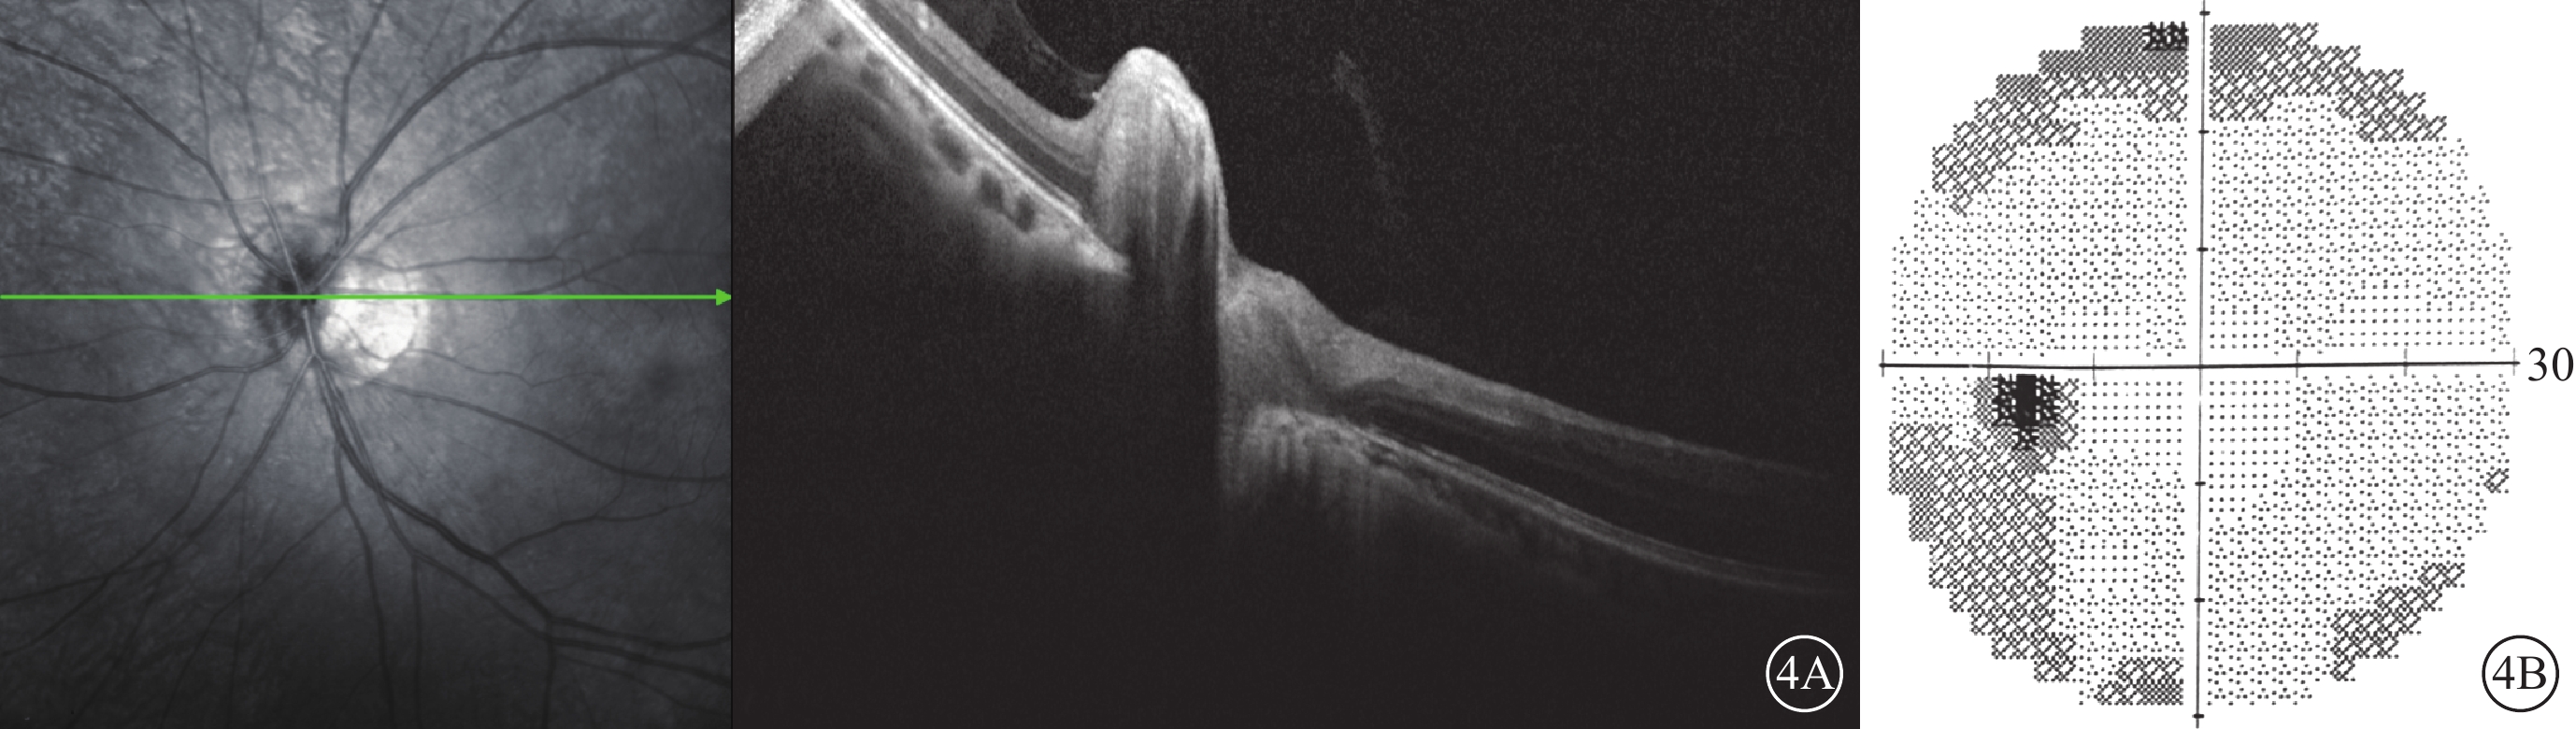

患者女,36歲。因接種人乳頭狀病毒(HPV)疫苗后1周出現左眼視物模糊、視物遮擋感,逐漸加重伴有眼球轉動痛于2020年5月16日就診于西安市人民醫院(西安市第四醫院)眼科。既往有口干、眼干病史。眼部檢查:左眼相對性瞳孔傳入障礙(+);右眼最佳矯正視力(BCVA)-3.50DS/-0.50DC×30°→1.2,左眼BCVA -3.00DS/-1.00DC×30°→0.15;右眼眼壓19 mmHg(1 mmHg=0.133 kPa),左眼眼壓19.3 mmHg。雙眼外眼及眼前節均無異常。眼底彩色照相檢查,右眼視盤邊界清楚;左眼視盤鼻側邊界模糊不清(圖1A),雙眼視盤顳側萎縮弧,視網膜平復,黃斑中心凹反光存在,視網膜未見出血、滲出。右眼光相干斷層掃描(OCT)、視野及視覺誘發電位(VEP)檢查結果均正常。左眼OCT檢查可見視盤顳側神經纖維層增厚(圖1B);視野彌漫性視野缺損(圖1C);圖形VEP、閃光VEP峰時延遲,振幅降低。熒光素眼底血管造影(FFA)檢查,雙眼臂-視網膜循環時間正常,視網膜血管熒光素充盈良好,視盤及視網膜動靜脈無熒光素滲漏。眼眶磁共振成像(MRI)檢查,左側視神經眶內段增粗,T2WI強信號(圖2A~2C),視神經眶內段無強化(圖2D)。顱腦MRI檢查,雙側腦室旁多個邊界清楚的圓形T2WI強信號病灶(圖3A~3C),增強檢查病灶無強化(圖3D~3F)。腦脊液壓力、蛋白定量檢測結果正常。血清白細胞計數0個/cm3;血清水通道蛋白4(AQP-4)抗體、髓鞘少突膠質細胞糖蛋白(MOG)抗體陰性;血清和腦脊液寡克隆區帶陰性。風濕免疫檢查血清抗單鏈結合蛋白(SSB)抗體陽性。診斷:左眼視神經炎、多發性硬化(MS)、干燥綜合征、屈光不正。給予甲潑尼龍500 mg/d,階梯遞減治療。治療1周后,右眼、左眼BCVA分別為1.2、0.8。治療1個月后,右眼、左眼BCVA分別為1.2、1.0;OCT檢查,左眼視盤顳側神經纖維層厚度正常(圖4A);視野檢查,左眼鼻下相對暗點(圖4B)。